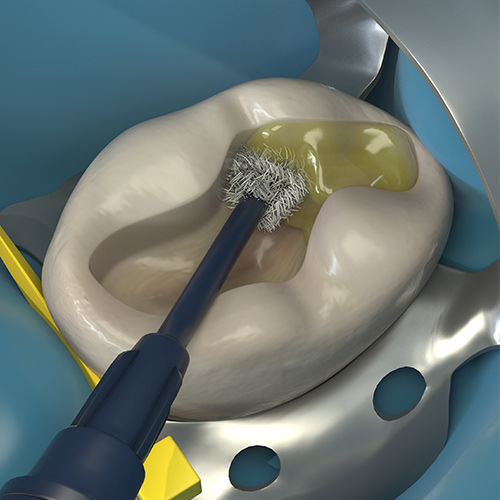

One-Day Endo-Restorative Treatment: The Integration of Advanced Technology and a Single-Visit Workflow for General Dental Practitioners

Scott Sayre, DDS, MBA, MAS

Monday, February 26, 2024

This Compendium eBook offers a continuing education (CE) article that explores the integration of technology as part of a single-visit workflow for root canal therapy that can be implemented by the general dentist. Download to earn 2 complimentary CEU now!